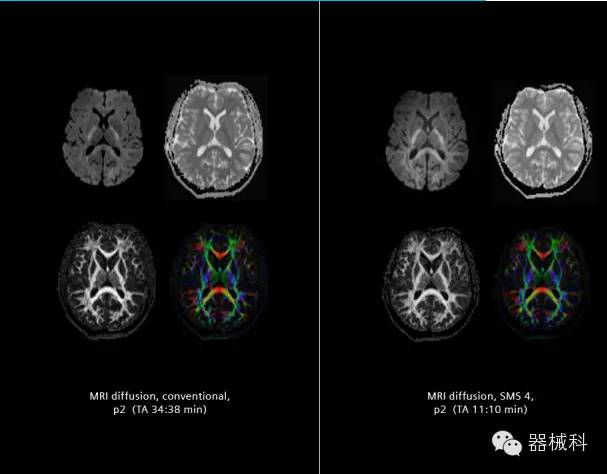

在2015年RSNA上,西門子隆重發(fā)布了Simultaneous Multi-slices 技術(即同時多層采集技術,簡稱SMS),這是磁共振掃描技術中第一次引入“同時多層”的概念,此概念技術的發(fā)布,將對未來磁共振成像領域帶來巨大的變革!

SMS將高級成像技術,尤其是神經(jīng)系統(tǒng)彌散成像時間縮短68%。

SMS技術可以將原本用于科研的高級成像技術轉化成臨床常規(guī)。

擁有了SMS“同時多層”采集技術之后,用戶可以在非常短的時間內(nèi)完成MR掃描,結合西門子靜音技術,大大提高患者的舒適性,或在單位時間內(nèi)采集更多的數(shù)據(jù),也可以得到高精度、高準確性、大數(shù)量的功能成像數(shù)據(jù),為臨床和科研提供強大的支持。專家認為,SMS“同時多層”采集技術未來在 提高成像質(zhì)量、外科手術計劃、降低術后神經(jīng)功能缺陷、提高fMRI的時間采集效率、提高靜息態(tài)功能磁共振數(shù)據(jù)質(zhì)量等方面將帶來深遠影響,希望該技術可以盡早面世,引領磁共振進入多層時代!